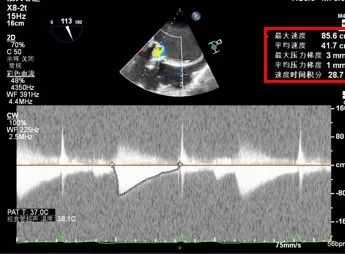

超声检查

诊断结果:

主动脉瓣置换术后,主动脉瓣前向血流速度加快并中-重度反流;

二尖瓣置换术后,二尖瓣重度反流;

三尖瓣修复术后,重度肺动脉高压并三尖瓣中-重度反流(符合危急值);

左房、右房扩大;

左室收缩功能正常低值。

术后TEE